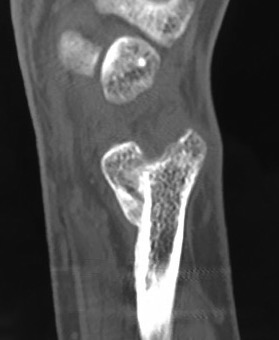

Xray

DRUJ instability

Post traumatic distal ulna osteoarthritis